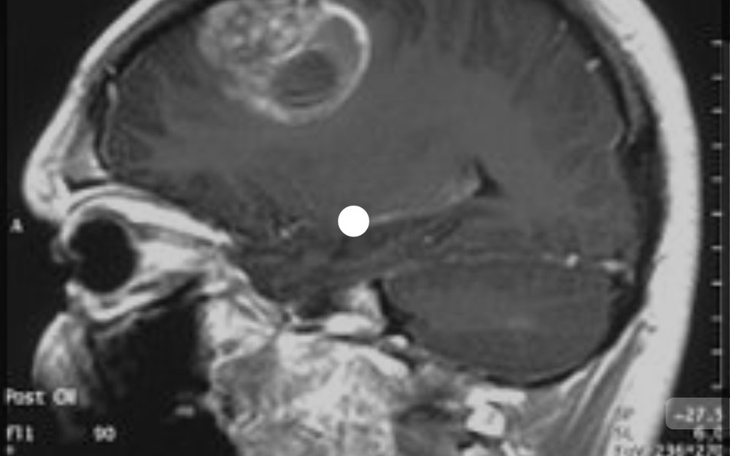

Mam na imię Patrycja, mam 29lat. Nigdy nie spodziewałam się, że będę musiała prosić Was o pomoc... Zawsze to ja pomagałam innym dziś niestety jest inaczej i to ja proszę o pomoc was. Nigdy nie wiemy, co przyniesie życie. A mi przyniosło brutalną wiadomość odnośnie zdrowia mojego Tatusia ... Od paru miesięcy Tata Walczy ze złośliwym guzem mózgu, który zajął już większą część lewej półkuli i dalej szybko rośnie! Tylko nierefundowana operacja może uratować mu życie!

Przez całe życie Tata był dla mnie bohaterem i wzorem do naśladowania. Dziś w wieku 51 lat ten bohater zaczął przegrywać walkę. Stan zdrowia bardzo się pogorszył mam zaledwie pare dni uzbieranie brakującej części pieniędzy potrzebnych na operacje. Bardzo proszę o pomoc.